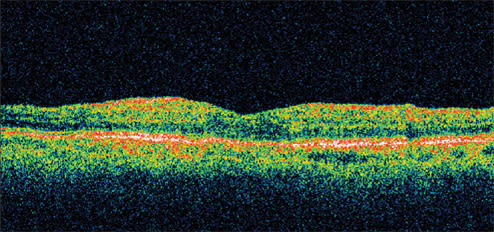

Figure 1. A 78-year-old woman complained of reduced visual acuity and contrast sensitivity OD 5 weeks after cataract surgery. Her presenting visual acuity was 20/40. Her IOP was 23 mm Hg, and retinal thickness was 478 μm on OCT.

A 78-year-old woman, with a history of cataract surgery, complained of reduced visual acuity and contrast sensitivity OD 5 weeks following surgery. She had a history of increased IOP, thought to be associated with steroid use, requiring medication following cataract surgery in the fellow eye. Her postoperative medication regimen consisted of a lowdose steroid taper.

Presenting visual acuity was 20/40. Her IOP was 23 mm Hg and retinal thickness was 478 μm on OCT (Figure 1). She was treated with nepafenac qid for 6 weeks and tapered over the ensuing 6 weeks. Her vision improved to 20/25 by 1 month with significant reduction in her retinal thickness (Figure 2). By 12 weeks, her visual acuity had improved to 20/20 with a retinal thickness of 216 μm and a normal foveal contour. This represents a reduction in retinal thickness of 262 μm from her pretreatment status (Figure 3). However, she continued to report a mild reduction in contrast sensitivity.